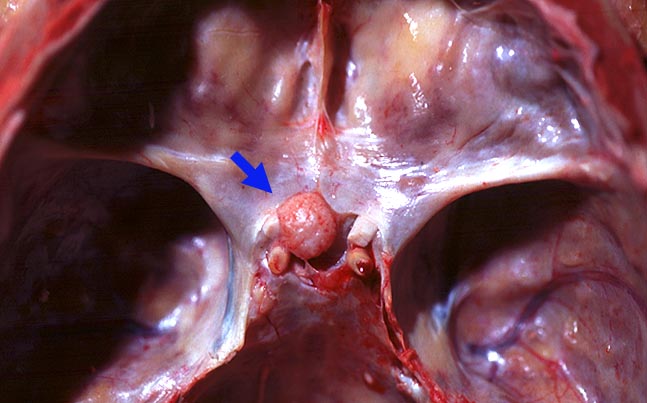

Die meisten Meningeome sind gutartig und fallen in die Kategorie WHO Grad I. Atypische Meningeome (WHO Grad II) machen zwischen 4.7-7.2% aller Fälle aus, anaplastische Menigeome (WHO Grad III) sind noch seltener. Meningeome sind oft multipel bei Patienten mit hereditärer Prädisposition und bei Neurofibromatose 2 sowie bei 10% der sporadischen Fälle. Meist wachsen Meningeome langsam. Sie sind in der Regel scharf begrenzt und sitzen der Dura breitbasig auf. Das Einwachsen von Meningeomgewebe in die Dura mater und/oder die benachbarte Schädelkalotte ist noch kein Malignitätszeichen und noch durchaus vereinbar mit einem benignen Meningeom WHO Grad I. Demgegenüber ist das Einwachsen in das benachbarte Hirnparenchym in aller Regel atypischen oder anaplastischen Meningeomen vorbehalten. Die Konsistenz ist prall-elastisch oder fest und das Tumorgewebe kann fokal verkalkt sein. Das Meningeom en plaque bedeckt flächenhaft die Dura als dünne Platte.

• Der Dura breitbasig aufsitzender scharf begrenzter halbkugeliger Tumor.